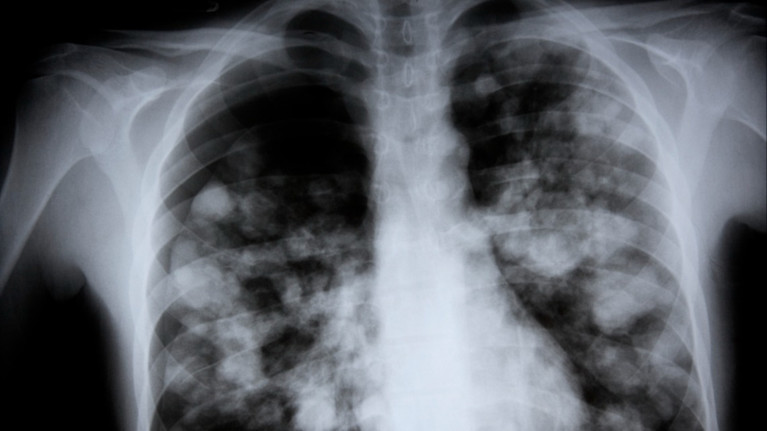

La neumonía es una acumulación de líquido espeso en los pequeños sacos de los pulmones llamados alvéolos. Suele producirse en bolsas en uno o ambos pulmones. Se denomina consolidación pulmonar. Aparece con bastante claridad en una radiografía de tórax.